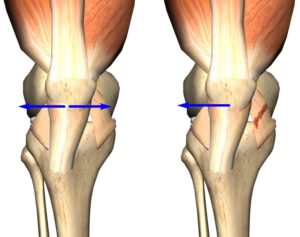

Нестабильность надколенника. Нестабильность надколенника это состояние, при котором надколенник стремится сместиться из центрального положение в сторону.

Бывает гиперпрессия коленной чашечки, то есть повышенное давление на суставную фасетку — латеральная гиперпрессия, то есть повышенное давление на наружный мыщелок бедренной кости, медиальная гиперпрессия, то есть повышенное давление на внутренний мыщелок бедренной кости. При латеральной гиперпрессии надколенник давит на наружную фасетку, при ещё большем смещении — появляется подвывих надколенника, при полном смещении – вывих.

Слабость внутренней удерживающие связки, слабость мышцы бедра, дисплазия мыщелков бедренной кости, высокое стояние надколенника, слабость или перенапряжение удерживателей надколенника и другие.

Анатомические особенности мыщелков бедренной кости играет ключевую роль в стабильности надколенника.

Существует дисплазия наружного мыщелка, при этом коленная чашечка легче смещаться кнаружи; дисплазия внутреннего мыщелка, при которой надколеннику проще смещаться кнутри.